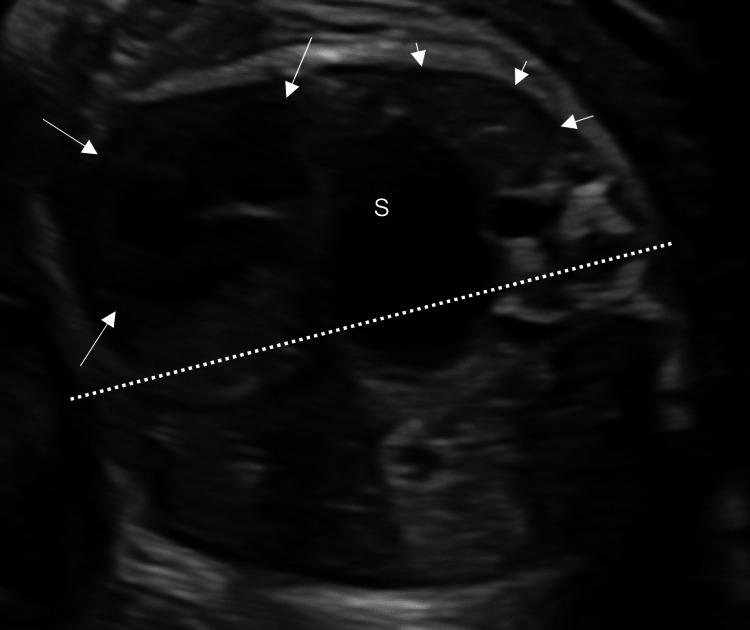

Congenital diaphragmatic hernia (CDH) is known to be complicated with various chromosomal abnormalities. However, the grade of pulmonary hypoplasia of CDH complicated by trisomy 9 is not known. This information is essential to the mother who has had a fetus with the same complication. We report a case of severe CDH with trisomy 9. The fetus had fetal growth restriction and multiple anomalies, including severe left CDH (observed/expected lung-to-head ratio 13.7%, liver-up, stomach grade 3 in Kitano classification), mild ventriculomegaly, low-set ear, rocker bottom, and single umbilical artery. Chromosomal test by amniocentesis showed a karyotype of 47,XX,+9. The neonate was born alive at 34 weeks but died 49 minutes after birth. In the literature review, this case and seven cases of complete trisomy 9 had CDH, and four of them were explained as "large" or "severe" CDH. In conclusion, trisomy 9 might be occasionally complicated by severe CDH.

先天性膈疝(CDH)已知会并发各种染色体异常。然而,9三体综合征合并CDH时肺发育不全的程度尚不清楚。这一信息对于怀有患有相同并发症胎儿的母亲至关重要。我们报告一例患有9三体综合征的严重CDH病例。该胎儿存在胎儿生长受限和多种异常,包括严重的左侧CDH(观察到的/预期的肺头比为13.7%,肝脏上移,北野分类中胃为3级)、轻度脑室扩大、低位耳、摇椅底足和单脐动脉。羊水穿刺染色体检查显示核型为47,XX,+9。新生儿在34周时存活出生,但出生后49分钟死亡。在文献综述中,该病例及7例9完全三体综合征病例患有CDH,其中4例被解释为“大型”或“严重”CDH。总之,9三体综合征偶尔可能并发严重CDH。